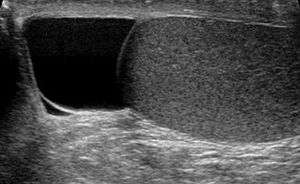

Ultrasound of a testicle (grey) and a spermatocele (black).

Finding a painless, cystic mass at the head of the epididymis, that transilluminates and can be clearly differentiated from the testicle, is generally sufficient. If uncertainty exists, ultrasonography of the scrotum can confirm if it is spermatocele.